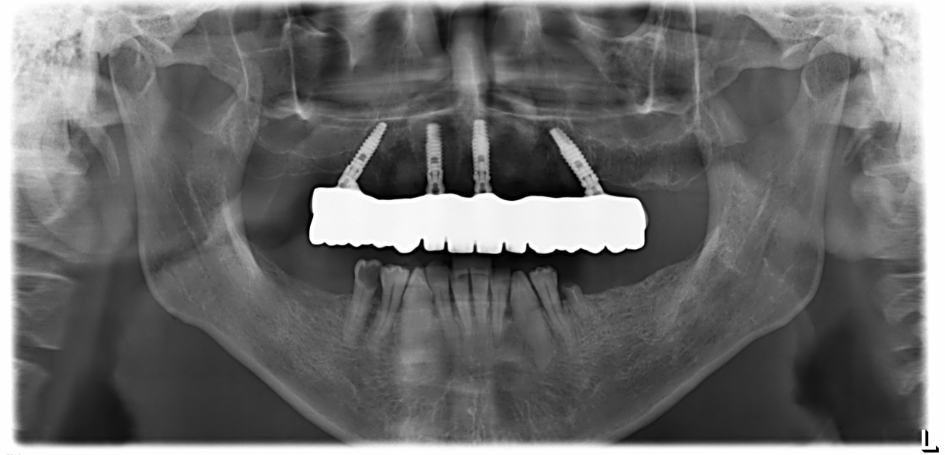

If all of the teeth are missing or need to be removed, you may be suitable for All On 4 dental implants, where all of the teeth are replaced using only four dental implants. To find out more about All On 4 treatment and if it’s a good option for your situation, it’s best to visit our Gold Coast All On 4 clinic for a complimentary consultation with our highly experienced team.